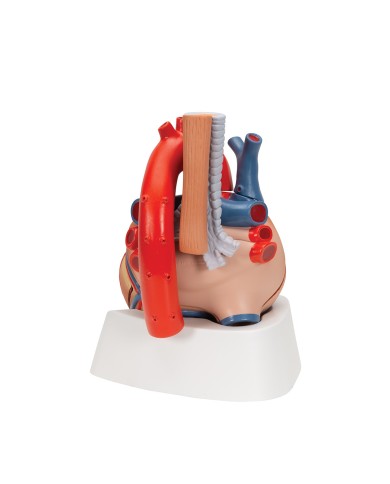

Modello anatomico di cuore, ingrandito 2 volte, su cavalletto

Questo modello dettagliato mostra, oltre alle strutture anatomiche del cuore, anche una parte del diaframma (base)